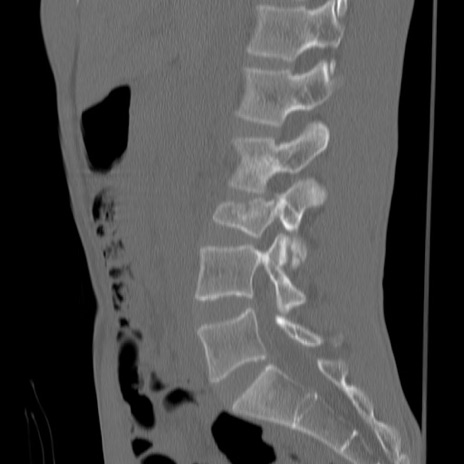

症例3 腰椎CT(矢状断像)

腰椎CT